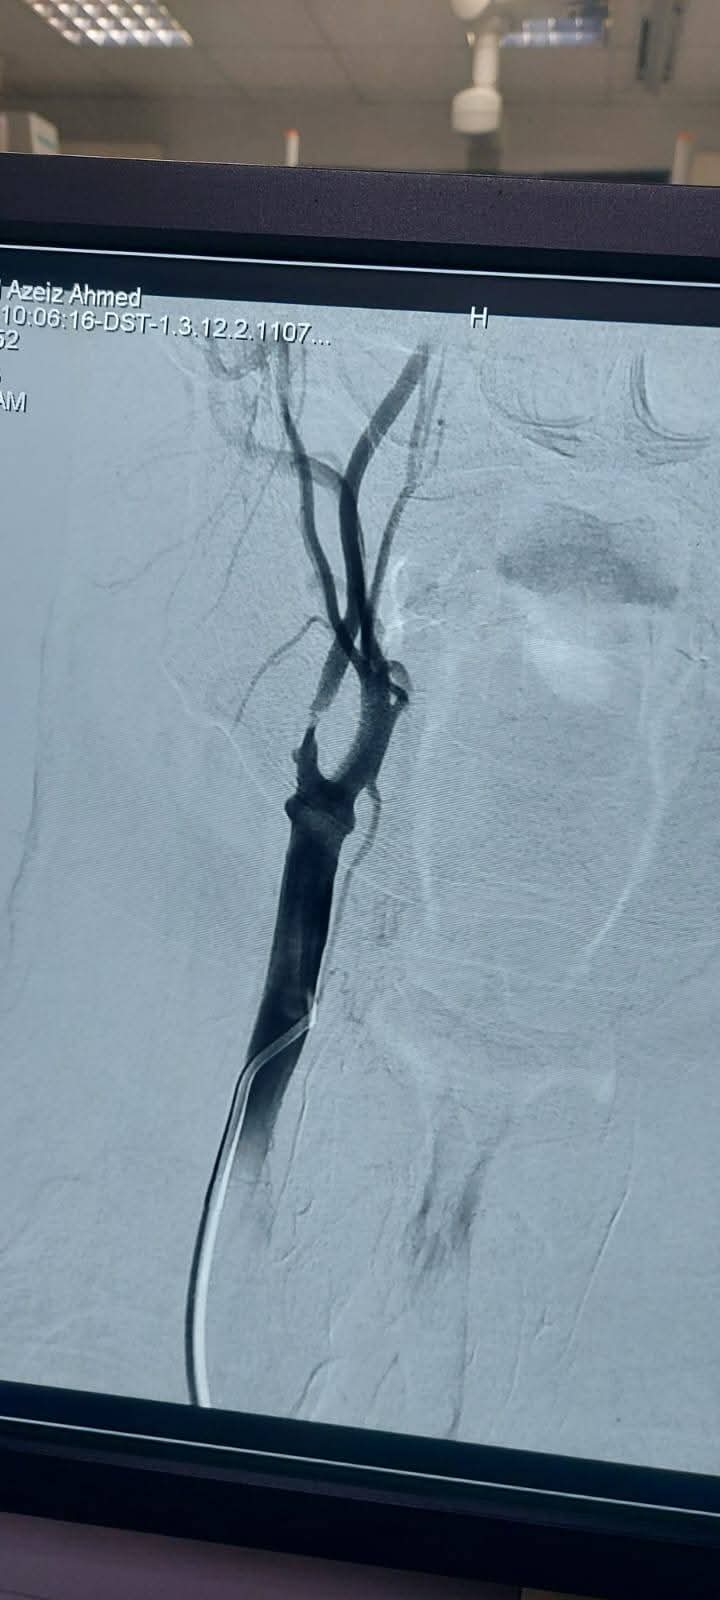

واستقبل المستشفى الرئيسي مريض يبلغ من العمر 65 عامًا، يعاني من جلطات متعددة بالمخ؛ نتيجة ضيق حرج بالشريان السباتي، وبعد إجراء الفحوصات اللازمة تقرر ضرورة التدخل بالقسطرة.

تشكل الفريق الطبي الذي جاء برئاسة الأستاذ الدكتور مصطفى هاشم أستاذ الأشعة التشخيصية والتداخلية والقسطرة المخية، يعاونه الدكتور محمود رفعت مدرس واستشاري الأشعة التشخيصية والقسطرة المخية، والدكتور محمود نجيب مدرس واستشاري الأعصاب والقسطرة المخية، والطبيب عبد الرحمن عمر مدرس مساعد الأشعة التشخيصية والتداخلية.